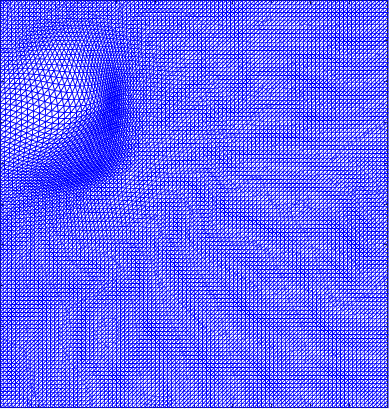

To better observe the result of our experiment, Figure 3 shows the second row of Table 2. The area bounded by the red box is the periphery of the beating heart. Figure 3(a) shows the ground truth frame. Figure 3(b) shows a frame with a perturbation combined with the normal deformation. The deformation between a frame and the reference image is computed by registration and represented by the Beltrami coefficient. Figure 3(c) shows the deformed image from the reference frame by the low rank part of the deformation. It closely resemble the ground truth frame as shown in Figure 3(a). Figure 3(d) shows the deformed image from the reference frame by the sparse part of the deformation. It demonstrates how the abnormal motion deforms the image from the reference frame. Thus, Figure 3(d) should be different from Figure 3(b), since Figure 3(b) combines both the normal and abnormal motions.

Figure 4 shows the visualisation of Figure 3 mappings in the form of grids. Let and be the Beltrami coefficients of the registration maps from the reference frame to the ground truth frame in Figure 3(a) and the perturbed frame in Figure 3(b) respectively. Figure 4(a) shows the mapping associated to Beltrami coefficient , and Fig 4(b) shows the mapping associated to BC . From Figure 4(c) and Fig 4(d), we can see that our method successfully restored the normal and abnormal deformation. Figure 4 serves as evidence that our decomposition is meaningful, in the sense that our method does not blindly return a Beltrami Descriptor with certain periodicity, but the decomposed descriptor does carry our desired information to recover the deformation to a large extent.